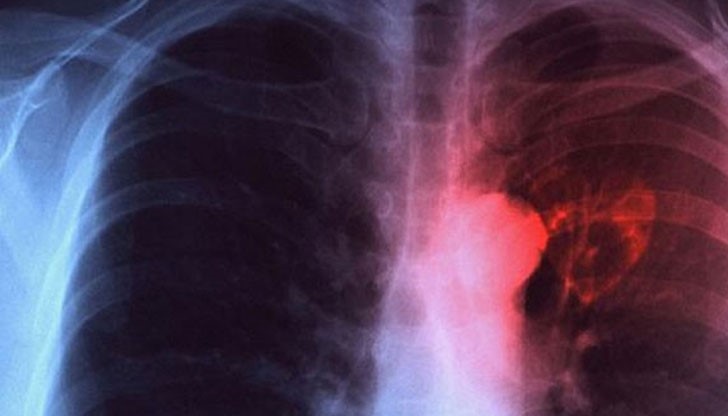

Световният ден за борба с туберкулозата се отбелязва от 1996 г. с решение на Световната здравна организация.

На този ден през 1882 г. немският бактериолог Робърт Кох обявява, че е изолирал бацила на туберкулозата. Затова си откритие Робърт Кох получава Нобелова награда за физиология и медицина през 1905 година.

Туберкулозата е огромно предизвикателство пред световното здраве. Всяка година в света се регистрират 9 милиона нови случаи на туберкулоза, съобщават от РЗИ- Русе, цитирани от ТОП НОВИНИ

Общият брой на болните с туберкулоза през 2014 г. в страната е 1 872 души, спрямо 3150 пациенти през 2008 година

В Русенска област като цяло намаляват новооткритите пациенти с туберкулоза, съобщават още от РЗИ. През 2015 г. са съобщени и регистрирани общо 43 болни от туберкулоза (заболяемост 18,89‰оо), като 18 от тях са с положително микроскопско изследване на храчка. През 2014 г. са били регистрирани общо 51 болни от туберкулоза (заболяемост 22,19‰оо), като 26 от тях са били с положително микроскопско изследване на храчка.

Очертава се трайна тенденция към понижаване на заболяемостта от туберкулоза.

През последните десет години заболяемостта се движи в следните граници – 51 случая (22,19‰оо) за 2014, 52 случая (22,46‰оо) за 2013 г., 55 случая (23,52 %000) за 2012 г., 56 случая (22,70 %000) за 2011 г., 74 случая (29,70 %000) за 2010 г., 75 случая (29,85 %000) за 2009 г., при 99 случая (39,13 %000) за 2008 г., 97 случая (37,99%000) за 2007 г., 45,94%000 през 2006 г., 33,95%000 през 2005 г., 40,21%000 през 2004 г., 44,66‰оо през 2003 г., 40,09‰оо през 2002 г. и 46,48‰оо през 2001 г.

Сравнително ниско е нивото на заболяемост в детската възраст, което е добър показател – регистрирани са 2 заболели деца от 1 до 4 г. и 3 деца от 15-19 г., като няма заболели във възрастовите групи 0-1 г., 5-9 г. и 10-14 г.

Задържа се тенденцията за поразяване на лицата в активна възраст при това социално- значимо заболяване. Разпределението на заболелите през 2015 г. по пол е следното: 26 мъже (61%) и 17 жени (39%). През 2015 г. няма починали от туберкулоза, докато през 2014 г. е починал един болен от туберкулоза (отчетена смъртност 0,44‰оо и леталитет 1,96%).